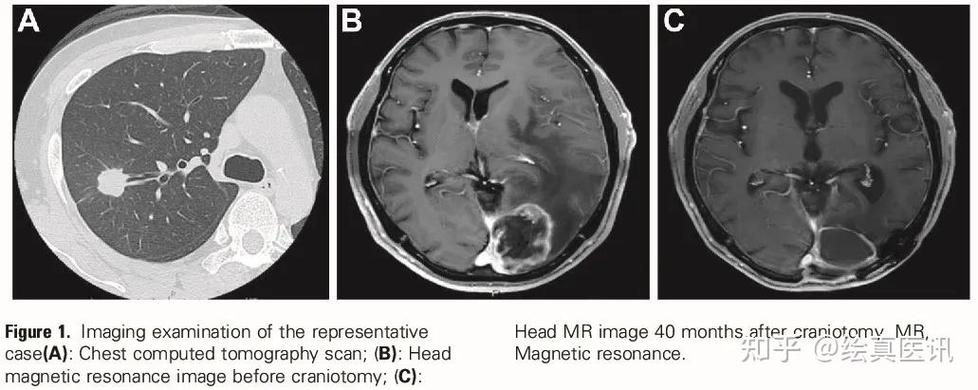

立体定向放射治疗(SRS/伽马刀):

- 优点:这是脑转移癌治疗的基石,它是一种高精度的放疗,像“狙击枪”一样,能精准地摧毁脑瘤,而对周围正常脑组织的损伤降到最低。

- 对于脑梗患者:如果脑梗是陈旧的(已经稳定),SRS通常是相对安全的选择,但如果脑梗是新鲜的或位于高风险区域,医生会非常谨慎,这是目前最常考虑的局部治疗手段。

- 精准影像:通过增强核磁共振(MRI)清晰地了解脑转移灶的数量、大小和位置,以及脑梗的部位和时期。